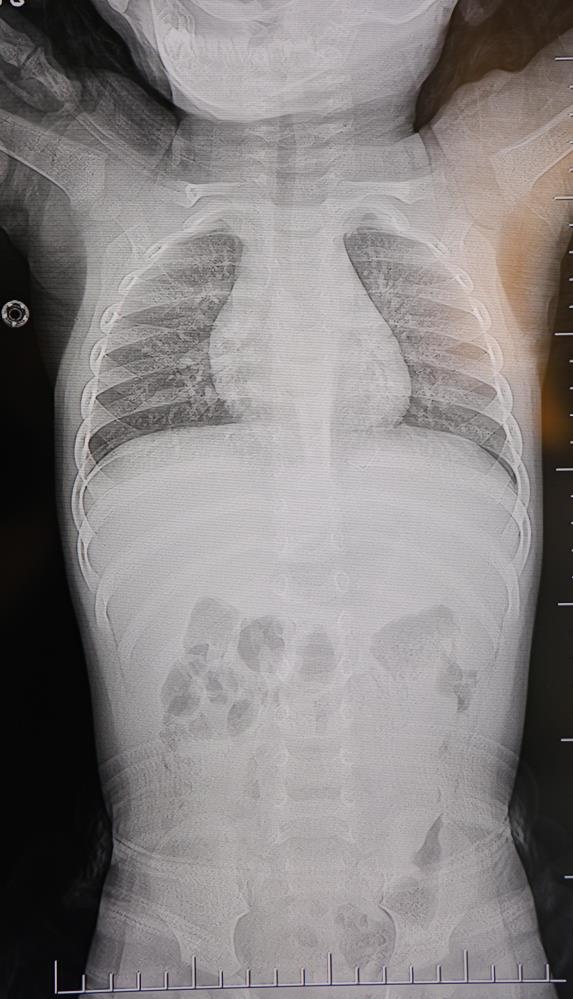

Beyin ve Sinir Cerrahisi Uzmanı Prof. Dr. İdris Altun tarafından yapılan tetkiklerde, yabancı cismin cilt altında, omurilik kanalına yakın bir bölgede olduğu ve akciğer zarına doğru ilerlediği belirlendi. Hasta, genel anesteziye alınmadan, lokal anestezi ve sedasyon eşliğinde ameliyata alındı. Yapılan müdahalede yabancı cisim tamamen çıkarıldı. Çıkarılan cismin, ince zımba teline benzer metal bir tel olduğu ve yaklaşık 2 santimetre uzunluğunda bulunduğu tespit edildi. Hasta, aynı gün taburcu edildi.

Konuya ilişkin açıklama yapan Prof. Dr. İdris Altun, "Sırtında yabancı bir cisim olduğu söylenmiş ancak çıkarılamayacağı ve 8 yaşına kadar beklenmesi gerektiği ifade edilmişti. Bize başvurduğunda yaptığımız tetkiklerde, cilt altında, omurilik kanalına çok yakın ve akciğer zarına doğru ilerleyen bir yabancı cisim tespit ettik. Hastamızı tamamen uyutmadan, lokal anestezi ve sedasyon eşliğinde müdahale ederek lezyonu tamamen çıkardık. Çıkardığımız cismin ince zımba teline benzer, yaklaşık 2 santimetre uzunluğunda metal bir tel olduğunu gördük. Bu yabancı cisim alınmasaydı, bölgede enfeksiyon gelişebilirdi. Enfeksiyon sonucu omurilik kanalında ciddi hasarlar oluşabilir, çocuk büyüdükçe cismin hareket etmesine bağlı olarak omurilikte zedelenmeler meydana gelebilirdi. Ayrıca yana doğru ilerleyerek akciğer zarına ve akciğere batma riski vardı. Bu da enfeksiyona ve ilerleyen süreçte tümörle karışabilecek tablolara neden olabilirdi. Şu an hastamız gayet sağlıklı. Gerekli kontrolleri yaptık ve aynı gün taburcu ettik" dedi.